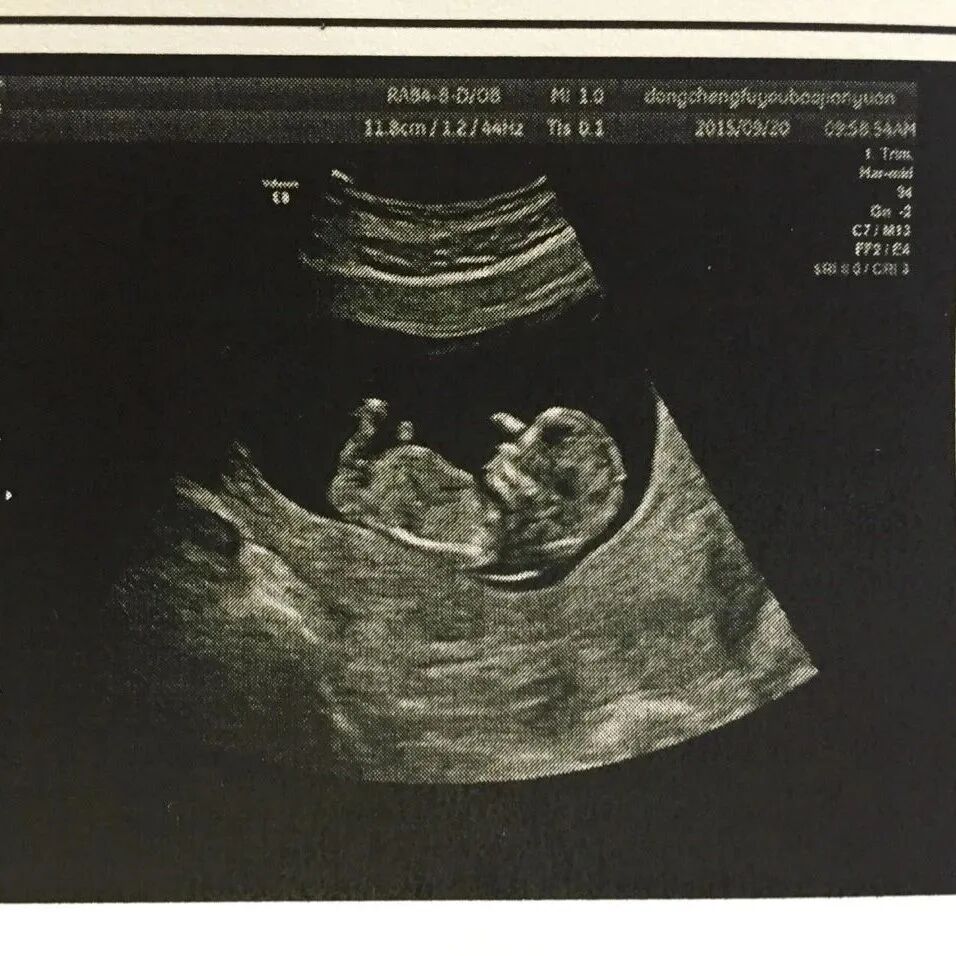

B超全称为B型超声,利用超声波在人体的组织中的反射、折射等物理特性,通过仪器接收信号,从而显示各种组织器官的形态,来判断病变部位、性质和功能损害的程度,这项技术在临床医学中用于早期明确诊断。

B超分为普通B超、彩色B超、三维B超和四维B超。普通B超为黑白,后三者均为彩色,三维B超和四维B超是目前比较先进的。

憋尿,男性在做泌尿系统及前列腺彩超检查时,需要充盈膀胱也就是需要憋尿后才可以进行检查。女性做盆腔(子宫附件)超声检查需要憋尿,准妈妈在孕12周+因为胎儿的快速发育,子宫隆起,就不需要在提前憋尿啦,随到随做就好。如果有极特殊的超声憋尿困难,如尿道炎的问题女性可选择阴式彩超(不用憋尿),但不适宜孕期使用。

超声检查对孕妇和孩子有影响吗?超声检查对人体都是没有电离辐射,目前没有科学证据证明彩色超声检查会对胎儿的生长发育带来不良影响,所以彩超诊断是医学影像学中无创、无辐射,而且最安全的诊断方法。